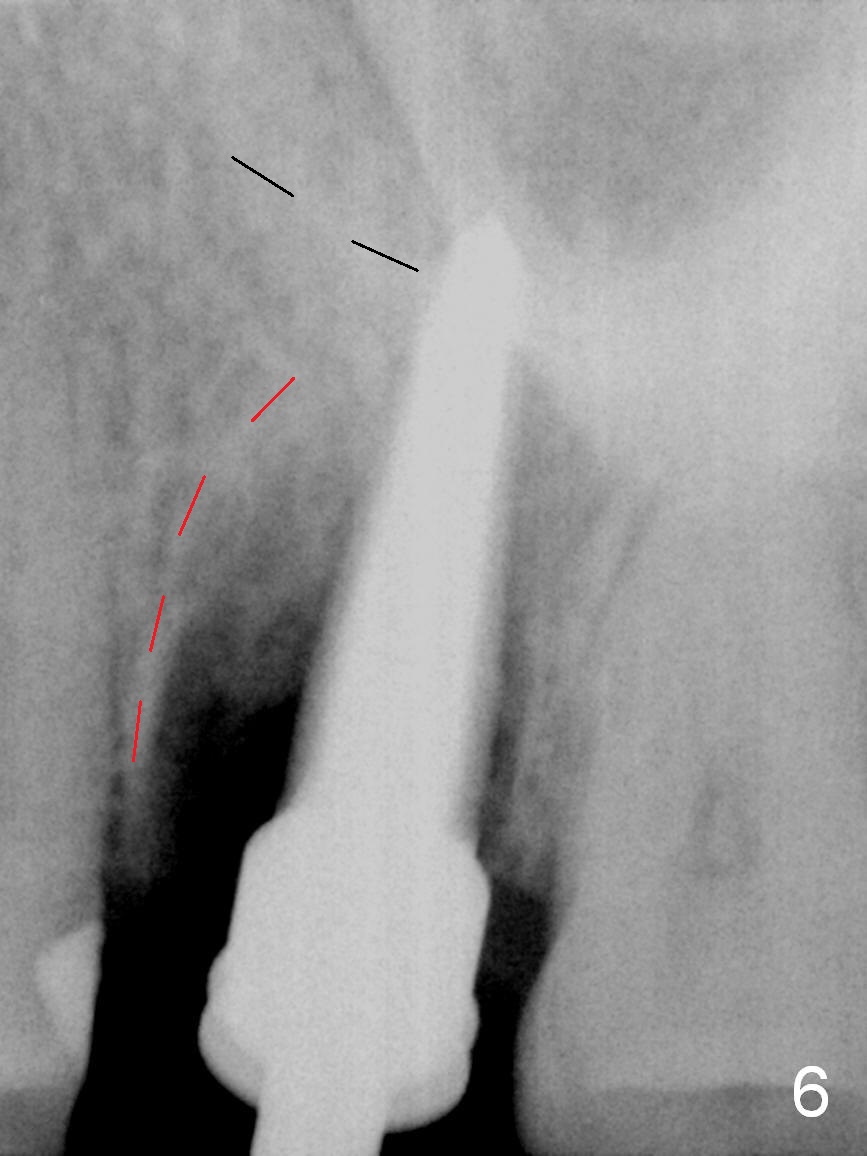

Preop CT shows that the septum appears to be able to hold a 11 mm long implant (Fig.1 sagittal section). There are periapical radiolucent lesions of the buccal (Fig.2 (coronal section) B) and palatal roots; bone height above the buccal apex is ~ 2 mm (Fig.3). When the tooth #14 is extracted, a 1.6 mm pilot drill is used to start osteotomy in the middle of the fairly thin septum (Fig.3 red line, Fig.4 S). It is hoped that Magic Expanders (ME) can enlarge the osteotomy by pushing the buccal and palatal bone plates of the septum outward (Fig.5 arrows).

The septal bone is dense and the osteotomy is enlarged by alternating use of drills and expanders. By the time 3.8 mm ME is tapped in (Fig.6), the buccal plate of the septum is perforated. The ME is stable, in spite of the fact that it is only supported by 2-3 mm bone buccally (Fig.7). Continuously alternating use of MEs and drills leads to placement of a 5x11 mm implant with 30 Ncm insertion torque and sinus lift. After placement of bone graft (Fig.8 *) and 5x4(3) mm pair abutment (A), an immediate provisional is fabricated. Red dashed lines in Fig.6,9 represent the mesial outline of the socket, whereas black dashed in Fig.6 sinus floor. It suggests that the implant is stabilized by relatively small amount of native bone. Although IBS implants have aggressive thread patterns, a proper apical osteotomy should be prepared in the depth (perforates the sinus floor in this case) and diameter (4.3 mm drill) prior to placement.